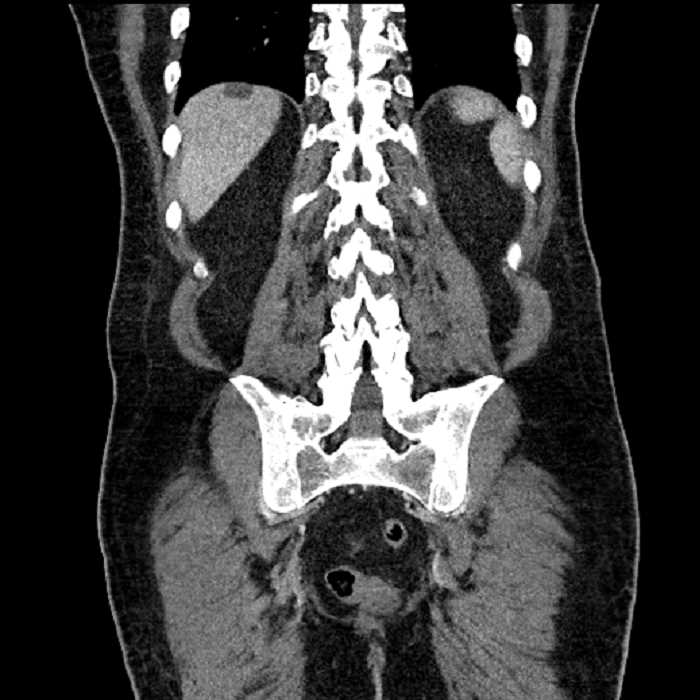

• High grade stenosis of the left common iliac artery, with the left internal and external iliac arteries remaining patent

• Ankylosis of both sacroiliac joints

High grade stenosis of the left common iliac artery. The left external and internal iliac arteries are patent.